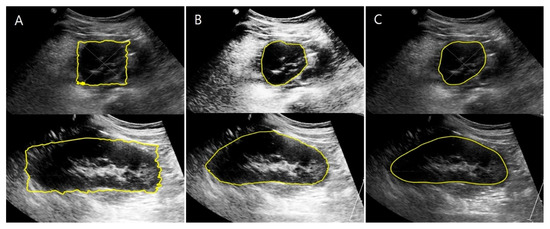

2.3.2. US Images and Image Processing Program

2.4.2. Data Augmentation Using Thin-Plate Spline Transformation